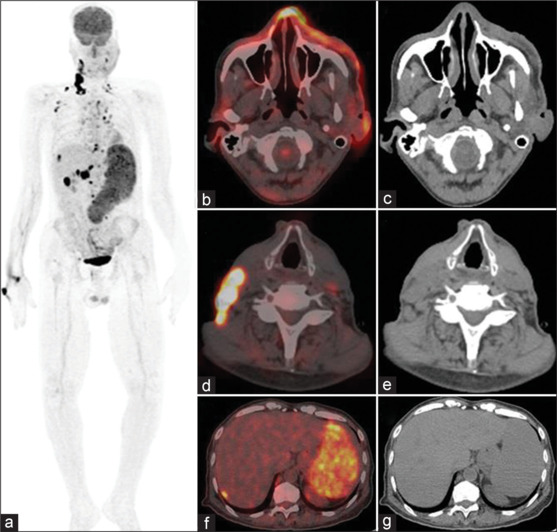

血管肉瘤是一种罕见的软组织肉瘤,仅占病理上起源于淋巴细胞或血管内皮细胞的软组织肉瘤的1%。据报道,血管肉瘤具有很强的侵袭性,转移到不同部位的发生率很高;因此,确定疾病的扩展范围,检测局部复发和/或远处转移,以进行适当的治疗是非常重要的。我们报告了一例55岁的印度男性,他表现为左脸颊软组织增厚,活检显示为血管肉瘤,并被推荐进行氟氧葡萄糖正电子发射断层扫描/计算机断层扫描(FDG PET/CT)以评估疾病的程度,强调FDG PET/CT在罕见恶性肿瘤(如血管肉瘤)中的潜在作用。

Angiosarcoma is a rare type of soft-tissue sarcoma, constituting only 1% out of all soft-tissue sarcomas pathologically originating from lymphatic or vascular endothelial cells. Angiosarcomas are reported to be very aggressive with a high incidence of metastases to different sites; therefore, it is very important to determine disease extension and detect local recurrence and/or distant metastases for appropriate management. We report a case of a 55-year-old Indian male who presented with soft-tissue thickening of the left cheek for which biopsy revealed angiosarcoma and was referred for fludeoxyglucose positron emission tomography/computed tomography (FDG PET/CT) to assess the extent of disease highlighting the potential role of FDG PET/CT in rare malignancies like angiosarcomas.